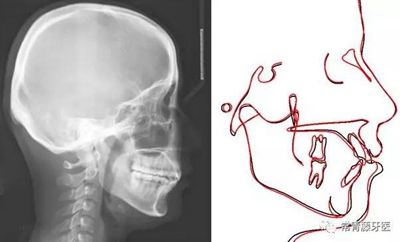

頭影測量顯示上下頜骨發(fā)育不足,且呈現(xiàn)骨性Ⅱ類。

術(shù)前術(shù)后描記圖顯示上牙列整體遠(yuǎn)移有效,表現(xiàn)為磨牙遠(yuǎn)移及上前牙內(nèi)收(黑色術(shù)前,紅色術(shù)后)。